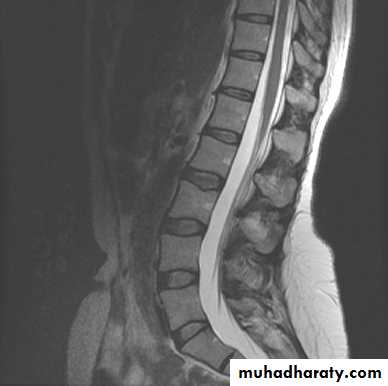

AT1-weighted images is one in which the contrast between tissues due mainly to their T1 relaxation propereties ,while in a T2-weighted image the contrast between tissues due mainly to their T2 relaxation propereties .

Most pathological processes show increase T1 and T2 relaxation times and these processes therefore appear lower in signal (blacker )on a T1 –weighted scan and higher in signal (whiter ) on a T2 –weighted scan than the normal surrounding tissue

T1 weighted images used for anatomical details (normal stracture )and T2 weighted images used for pathological processesMRI SCANNER